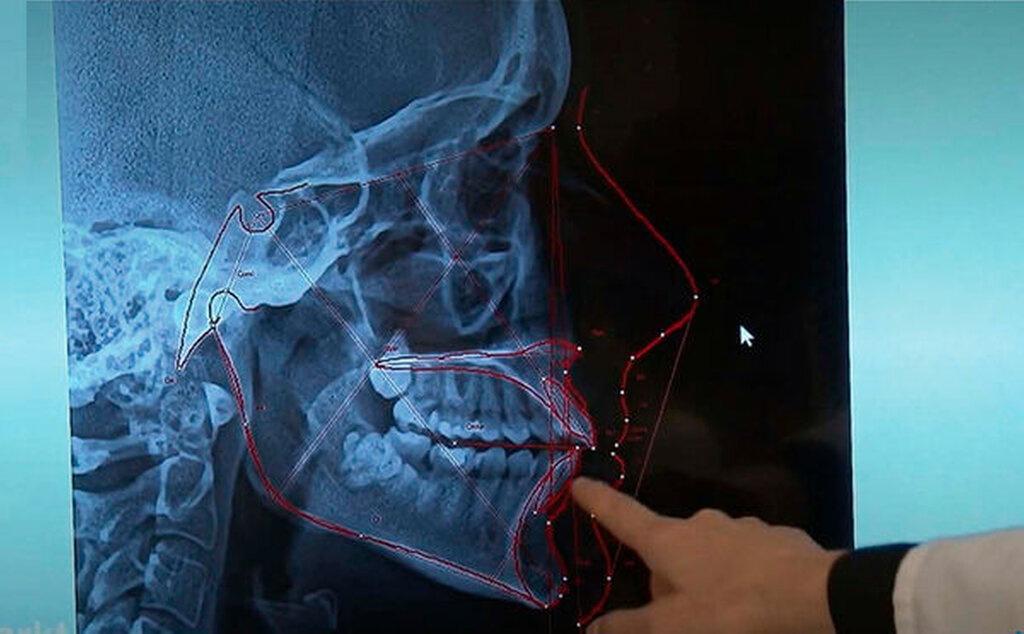

Ja, eindeutig. In der Regel sind es schon Fehler bei der Diagnostik: fehlende Diagnostik, kein Röntgen, keine Modellanalysen, kein FRS, keine funktionelle Untersuchung, eine Diskrepanz RKP/IKP wurde gar nicht erkannt, weil überhaupt nicht untersucht. Daraus resultieren dann Fehler bei der Planung: Jemand plant, der den Patienten nicht untersucht hat, alle wichtigen Informationen für die Planung fehlen. Ganz offensichtlich planen dort Leute, die keine Ahnung von Biomechanik und KFO haben, denn es werden Bewegungen geplant, die gar nicht realistisch sind beziehungsweise parodontalschädlich sind. Es fehlen die notwendigen Attachments, es werden gleichzeitige Bewegungen gemacht, die nicht möglich sind, es fehlt bei der Planung das Verständnis für die notwendige Verankerung für Zahnbewegungen. Aus Planungsfehlern werden dann Behandlungsfehler: Wenn die Aligner im distalen Bereich nicht passen, werden sie einfach abgeschnitten, was fatale Folgen hat. Auch dafür fehlt offenbar jedes Verständnis.